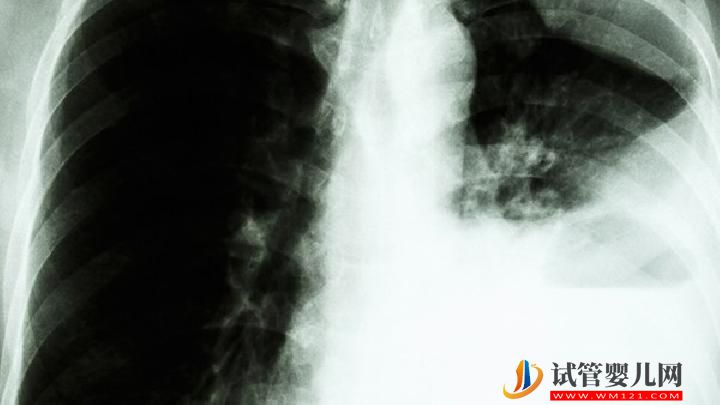

肺癌患者可以過性生活嗎?你知道為什么肺癌不傳染嗎?

為什么肺癌不傳染?